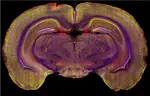

Investigating the roles of translin/trax, a microRNA-degrading enzyme in the brain and beyond

Post-Traumatic Stress Disorder (PTSD)

Development of a rat model of Post-Traumatic Stress Disorder (PTSD)

Ovarian Hormones and Antidepressants

Influence of ovarian hormones on antidepressant drug treatment

Vagal Nerve Stimulation

Mechanisms underlying the anxiolytic and antidepressant effects of vagal nerve stimulation, an FDA-approved therapy for treatment-resistant depression